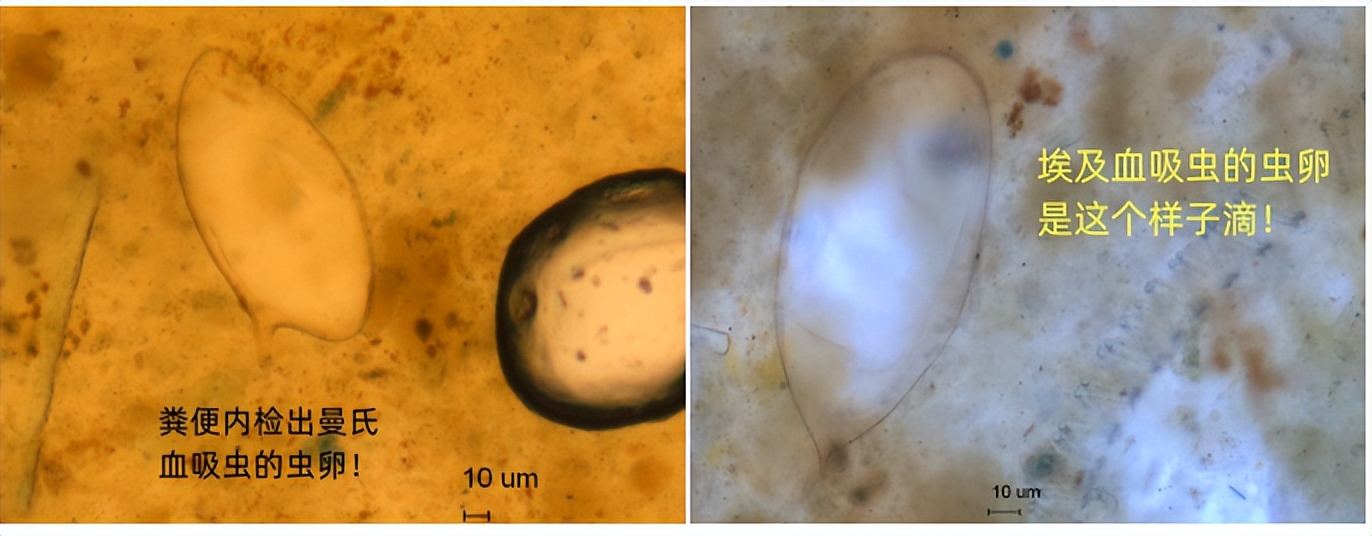

除输入性疟疾外,输入性的皮肤利什曼病、埃及血吸虫病、曼氏血吸虫病等也均曾在我们门诊被诊断发现,有些病例感染后经过了长达十年多家医院的诊疗最终才被确诊,给病人带来了巨大的健康损害和经济损失。所以,归国人员出现不明原因的发热、皮肤病变、血尿、嗜酸性粒细胞增多等异常临床表现,排除医院常见病后也应关注是否有寄生虫的感染。

6.粪便检测: 可通过肠道粪便排出体外的寄生虫的成虫、虫卵、包囊和滋养体(钩虫、蛔虫、鞭虫、蛲虫、肝吸虫、血吸虫、姜片虫、阿米巴、蓝氏贾第鞭毛虫病等)。